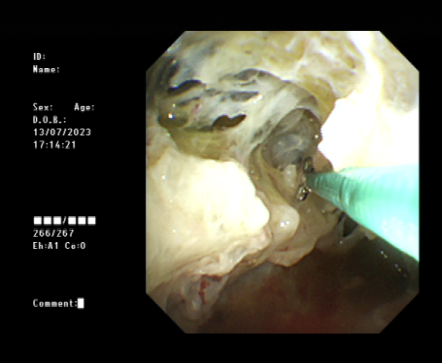

近年来,贵州航天医院各科室紧跟医学前沿,不断强技术、补短板,大力开展新技术、新项目,完成了许多高精尖、高难度、本地区“首例”的技术,填补了医院医疗技术空白,满足了群众日益增长的医疗需求。 贵州航天医院呼吸与危重症医学科是贵州省内呼吸疾病治疗规模最大,诊疗项目最全的呼吸疾病品牌科室,呼吸介入技术达到了全国先进水平,在贵州省内处于领先的地位。 本期,我们将为大家带来呼吸与危重症医学科特色技术——内科胸腔镜技术诊断和治疗胸腔疾病。 案例分享 患者苟某某,因劳累、气促,不明原因胸腔积液在某县一医院采取反复抽水等治疗手段效果不佳,当地医院考虑到患者年龄大(77岁),基础疾病较多,病情复杂,结合当地诊疗水平能力情况,建议转到上一级医院诊治,通过我院与该院建立的呼吸专科联盟绿色通道转入了我院。 患者入院后,呼吸与危重症医学科第一时间复查胸部CT,提示:右肺中叶、左肺感染,纤维化灶,左侧中量胸腔积液,右后侧胸膜轻度增厚,心包少量积液;并完善心电图、血常规、凝血功能、生化指标等术前检查。经科室专家团队集体讨论,得出患者左侧胸腔积液可能原因:结核?恶性?其他?冠心病、心功能不全、高血压病3级(高危组)、陈旧性肺结核复发?肺部感染;为进一步明确诊断,在充分评估、做好术前准备及应急预案、与患者及家属沟通的情况下,决定为患者进行内科胸腔镜检查术。 科室在患者入院第3天便实施了内科胸腔镜检查术,经检查取活检,病理不排除胸膜间皮瘤,送遵义医科大学附属医院病理会诊后诊断:胸膜间皮瘤。明确诊断后,科室专家团队为患者制定了个体化的治疗方案,患者病情很快得到有效控制,最终满意出院。半年后,医院通过电话回访,患者病情稳定,生活质量明显改善。 什么是内科胸腔镜 内科胸腔镜(medical thoracoscopy,MT)是一项微创诊断和治疗胸腔疾病的重要技术。主要应用于无创方法不能确诊的胸腔积液和胸膜疾病,通过局部麻醉后在胸壁做一个小切口,插入胸腔镜,直接观察胸膜、肺表面、纵隔等部位的病变情况,可进行活检、粘连松解及胸膜固定等操作。具有创伤小、恢复快、诊断准确性高等优点。 内科胸腔镜原理 内科胸腔镜是一项利用现代光学技术和成像技术的侵入性操作技术,应用电子支气管镜、硬质或软硬结合(半硬)的胸腔镜的一种电子内窥镜,末端装有连接着显示屏的微型摄像头。通过胸壁1-2cm左右的小切口,将内科胸腔镜及专用器械(戳卡套管)通过小切口进入胸腔,微型摄像头将胸腔内的情况投射到显示屏幕上,医生可以通过镜头全面、直观地观察患者胸腔内情况,了解胸膜病变确切位置和形态改变,还可对胸膜上的病变进行活检及治疗的操作技术,安全、微创、几乎无痛地“揭秘”不明原因的胸腔积液。 内科胸腔镜技术优势 (一)安全性高:仅需局部浸润麻醉,并发症发生率相对较低,对患者的身体条件要求较低。 (二)操作简便:操作时间短,痛苦少,患者耐受好。 (三)微创性:切口小,对患者身体损伤小,术后疼痛轻,恢复快。 (四)高分辨率成像:清晰显示胸腔内细微病变,提高诊断准确性。 (五)可直视操作:直接观察病变,进行精准活检和治疗。 (六)适用范围广:可用于不明原因胸腔积液、胸膜疾病、肺部疾病等的诊断和治疗。 (七)费用低:与外科胸腔镜比较费用低廉。 内科胸腔镜技术是贵州航天医院呼吸专科和呼吸介入诊疗优势的一部分,在2016年率先开展了内科胸腔镜技术,年手术量约100余例,已建立了快速、精准、规范、有效的一体化诊疗服务体系。目前呼吸与危重症医学科内科胸腔镜技术广泛应用于不明原因胸腔积液、气胸、脓胸的诊断和肺癌、弥漫性恶性胸膜间皮瘤等的分期,恶性或复发性胸腔积液、早期脓胸、自发性顽固性气胸的治疗。 镜下常见表现:单发或多发结节、灰白色弥漫性粟粒样结节、胸膜充血、水肿、胸膜增厚及纤维分隔或粘连带形成。 诊断方面: 胸腔积液的病因诊断。内科胸腔镜对恶性胸腔积液的诊断率可高达90%以上,胸腔镜对结核性病变诊断率极高,几乎达到96%以上。 腺 癌 恶性淋巴瘤 软骨肉瘤胸膜转移 滑膜肉瘤胸膜转移 结核性胸膜炎 治疗方面: 脓胸 肺大泡 贵州航天医院 呼吸与危重症医学科学科带头人 廖江荣 国务院政府特殊津贴专家 二级教授 主任医师 贵州航天医院副院长 国家级学术任职: 第二届中国医药教育协会介入微创专业委员会呼吸分会副主任委员 中国抗癌协会肿瘤微创治疗专业委员会常务委员 中国防痨协会结核病转化医学专业分会常务委员 第一届中国人体健康科技促进会呼吸介入专委会常务委员 中国医疗保健国际交流促进会结核病学分会第三届委员会常务委员 中国抗癌协会肿瘤微创治疗专业委员会粒子治疗学组第四届委员会委员 中华医学会结核临床专业委员会内镜介入委员 中华医学会放射学分会第十五届委员会介入学组呼吸系统介入专业委员会委员 北京健康促进会中青年专家委员会胸部疾病精准活检分委会副主任委员 中国医师协会介入医师分会第二届委员会肿瘤消融专业委员会委员 中国结核病防治综合质量控制专家指导委员会委员 亚洲冷冻治疗学会常务委员 世界内镜医师协会呼吸内镜协会常务理事 内镜临床诊疗质量评价专家委员会委员 “西部呼吸介入联盟”副理事长 专业擅长: 贵州航天医院 呼吸与危重症医学科简介 贵州航天医院呼吸与危重症医学科以呼吸危重症和介入呼吸病学为强力推手,以肺部感染性疾病及肺癌、肺小结节的早期精准诊疗、慢性呼吸疾病康复治疗为特色,以人才团队建设为核心的科室发展模式,现已成为省内呼吸疾病治疗规模最大,诊疗项目最全的呼吸疾病品牌科室。是贵州省医学重点学科、临床医学重点专科建设单位,遵义市首批呼吸重点学科、重点专科建设单位。是国家卫健委能力建设和继续教育肿瘤微创介入建设中心、贵州省县级医院微创介入培训中心、遵义市呼吸疾病临床医学中心。是国家呼吸医疗质量控制与管理哨点医院、遵义市呼吸内科专业医疗质量控制中心。是中国医药教育协会介入微创呼吸分会呼吸介入技术培训中心单位;国家卫健委海医会呼吸分会ROSE专委会“诊断性介入肺脏病学快速现场评价”培训基地;中国肺癌防治联盟“贵州航天医院肺结节诊治”分中心,中国人体健康科技促进会呼吸介入技术培训基地,贵州省中西医结合会呼吸学分会呼吸介入专委会主委单位。 基本情况 平均每年开展气管镜诊疗约4000例,经皮肺穿刺介入诊疗近千例,开展的项目包括经支气管镜(软、硬)下冷冻、氩气刀、高频电刀、球囊扩张、支架置入、超声内镜诊疗等气道介入诊疗技术,经皮肺穿刺活检及肿瘤消融术(微波、冷冻)、ROSE技术、内科胸腔镜诊疗及经血管介入诊疗技术,且多项呼吸介入诊疗技术在省内处于领先水平。 诊疗范围 航天医院呼吸专科擅长:致力于呼吸系统感染性、疑难性疾病的介入快速精准诊疗;肺癌与肺小结节早期精准诊疗水平项目提升。擅长于呼吸系统(肺)疑难病的诊断及危重病的救治,尤其在肺癌、肺小结节的早期诊断;肺癌综合靶向治疗;肺结核综合诊疗;肺部疾病的介入诊疗在省内处于前沿水平。 咨询热线 (一)呼吸与危重症医学科一病区 医生办公室:27677317 护士站:28614217 (二)呼吸与危重症医学科二病区 医生办公室:28691274 护士站:28690442 (三)呼吸与危重症医学科三病区 医生办公室:28692417 护士站:28690461 (四)呼吸与危重症医学科四病区 医生办公室:28616402、27677582 护士站:28614987、27677862